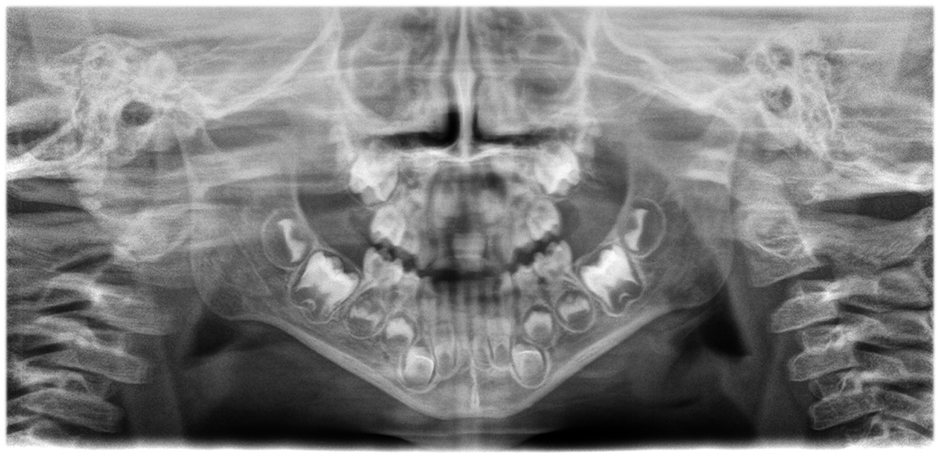

• Imágenes panorámicas de nitidez y definición extraordinarias

gracias al innovador sistema de enfoque automático de 21 capas integrado a la perfección con la corrección de posición del paciente.

Mueva el botón deslizante para ver la diferencia (a la izquierda, imagen sin enfoque automático; a la derecha, con enfoque automático y posición corregida del paciente).